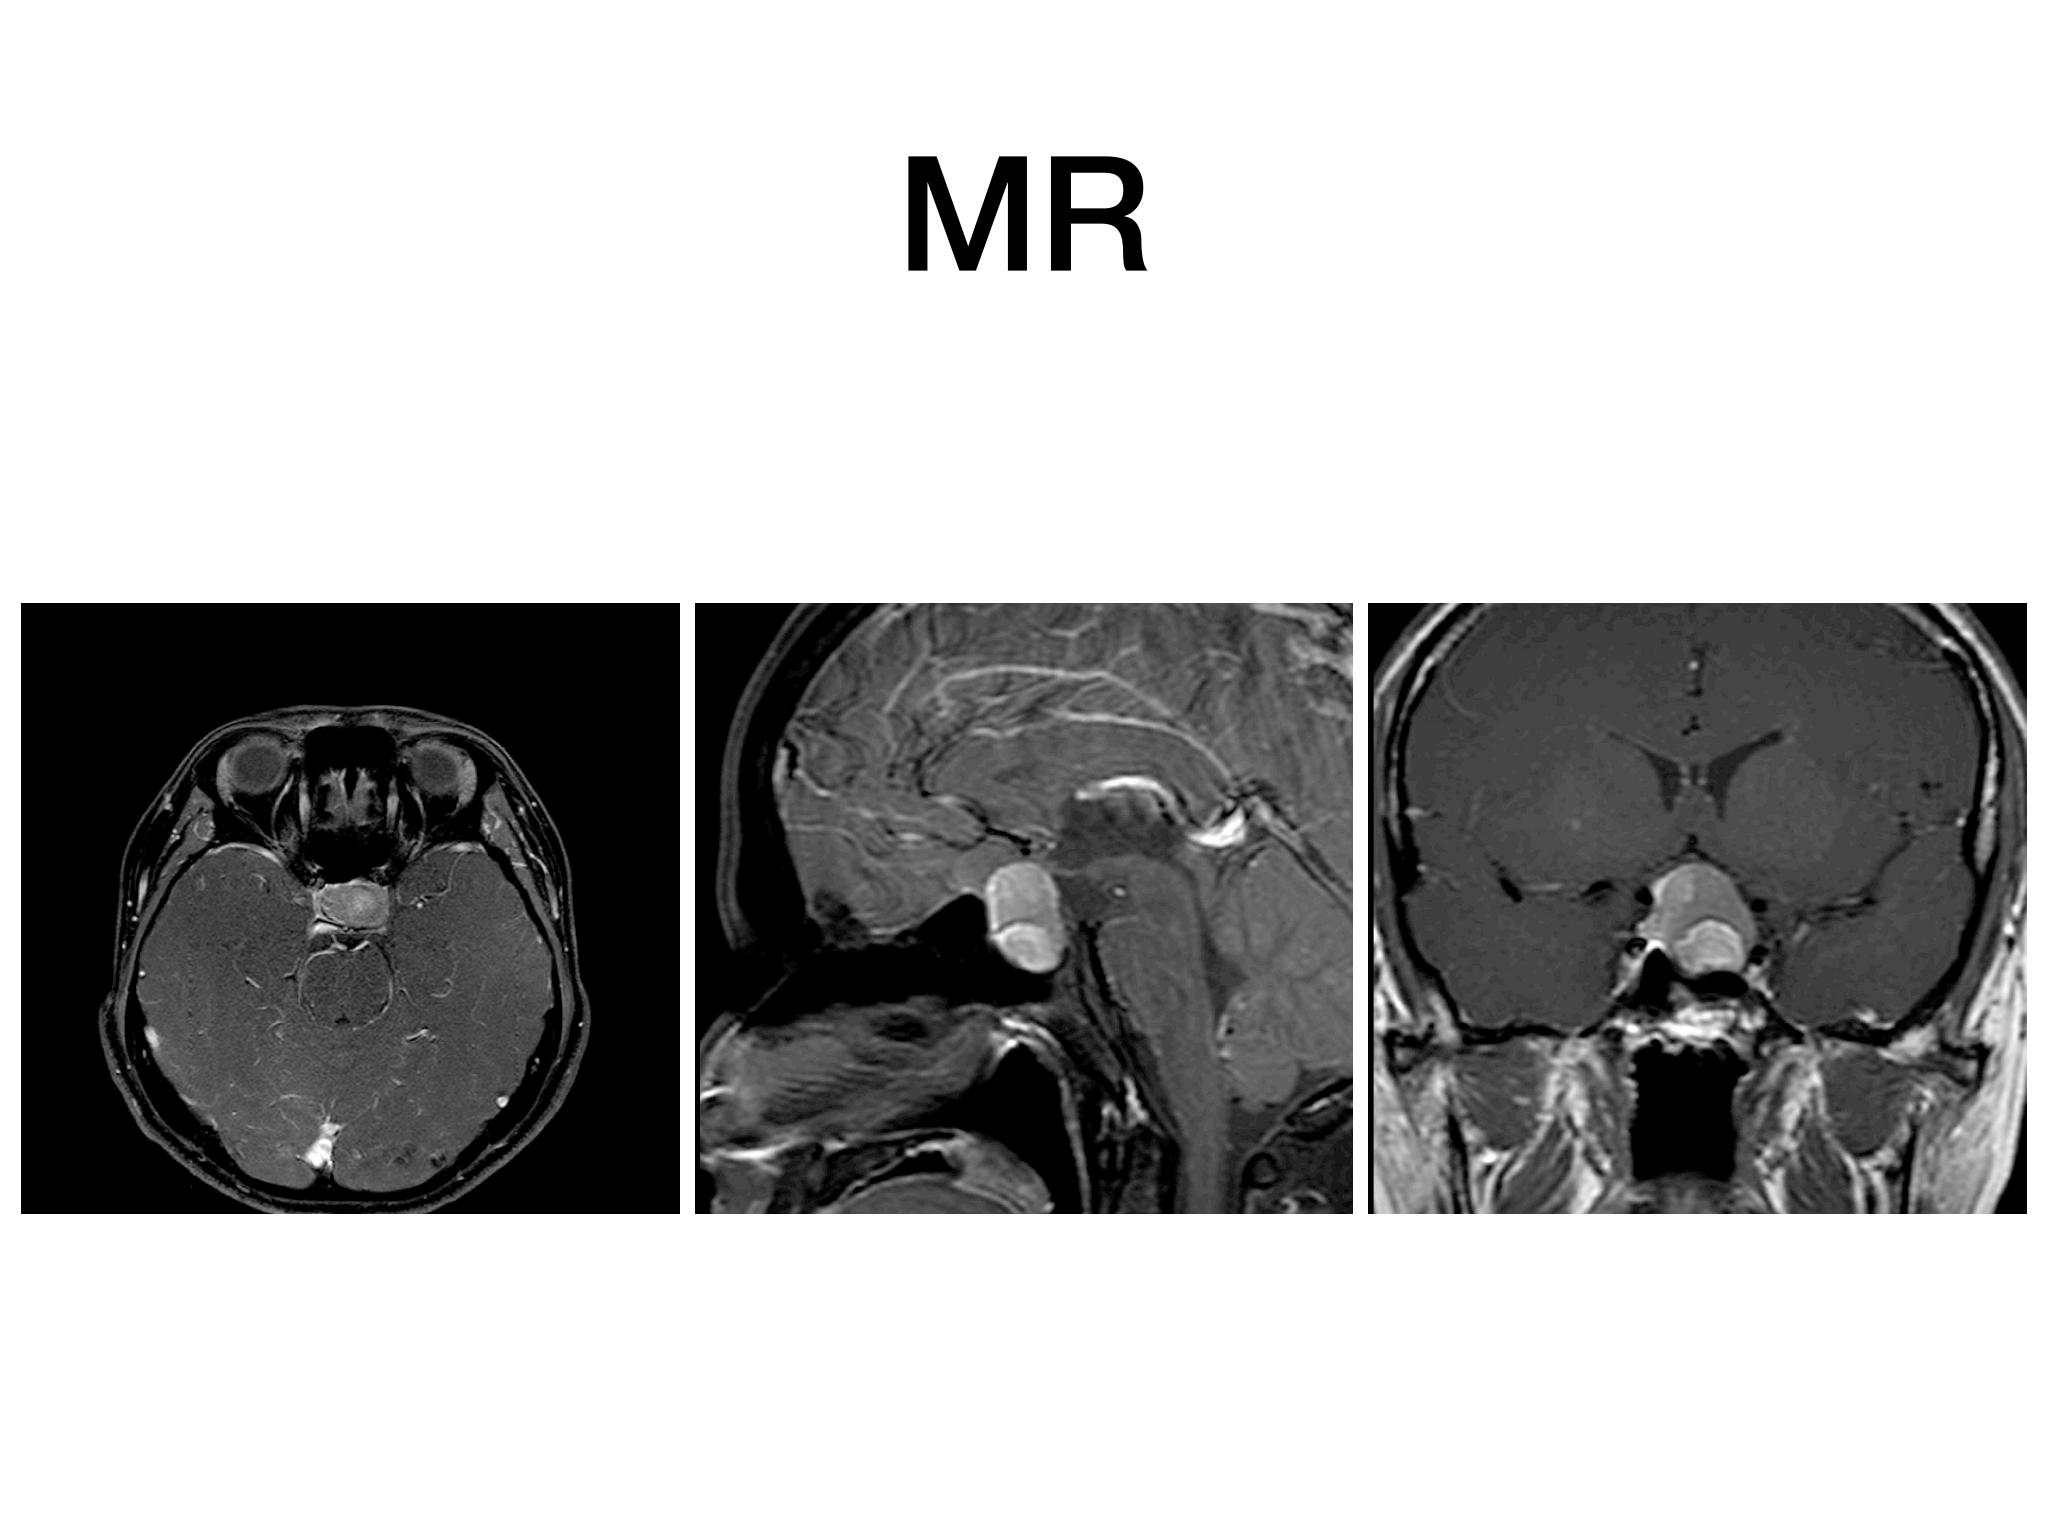

分享一例经鼻内镜泌乳素大腺瘤切除手术,患者青年男性,术前泌乳素>200ng/dl,MR提示大腺瘤合并瘤内出血,手术全切肿瘤,术后泌乳素降至正常,生化缓解,预后良好。